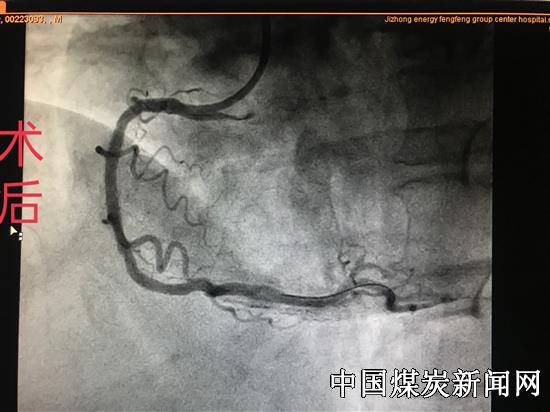

【本网讯】近日,冀中能源华北医疗健康产业集团峰峰总医院北院区心内科,独立成功为一名男性患者行药物球囊扩张治疗支架内再狭窄手术,手术过程顺利,术后患者恢复良好。此项新技术在本院区的独立完成,得到了业内知名专家和患者家属的充分肯定及认可!

患者男性,51岁,因冠心病于1年前在某医院行支架植入术,近日因反复胸闷、胸痛加重来我院心内科住院治疗。经科室副主任赵军峰及其主管医师会诊讨论后,决定为其行冠脉造影检查,检查结果显示患者右冠中段可见支架影,支架内狭窄。根据造影结果和病人自身情况该科医疗团队为其制定了科学的治疗方案,由该科副主任赵军峰及尹威、魏鹏辉医师为其行药物球囊扩张治疗支架内再狭窄手术。手术过程十分顺利,术后患者身体恢复良好,得到了患者及家属的高度认可和赞扬。此项技术不但解决了冠脉植入支架后再度出现血流不畅的诸多难题,同时,又大大提高了患者的生活质量。